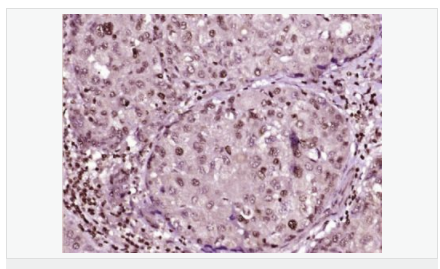

交叉反應(yīng):Human,Mouse,Rat(predicted:Dog,Pig,Rabbit,GuineaPig) 推薦應(yīng)用:IHC-P,IHC-F,ICC,IF,Flow-Cyt,ELISA

| 英文名稱 | phospho-HSP70 (Tyr611) |

| 中文名稱 | 磷酸化熱休克蛋白-70抗體 |

| 產(chǎn)品類型 | 磷酸化抗體 |

| 交叉反應(yīng) | Human, Mouse, Rat, (predicted: Dog, Pig, Rabbit, Guinea Pig, ) |

| 產(chǎn)品應(yīng)用 | ELISA=1:5000-10000 IHC-P=1:100-500 IHC-F=1:100-500 Flow-Cyt=1μg/Test ICC=1:100 IF=1:100-500 (石蠟切片需做抗原修復(fù)) not yet tested in other applications. optimal dilutions/concentrations should be determined by the end user. |

| 免 疫 原 | KLH conjugated Synthesised phosphopeptide derived from human HSP70 around the phosphorylation site of Tyr41:GL(p-Y)QG |